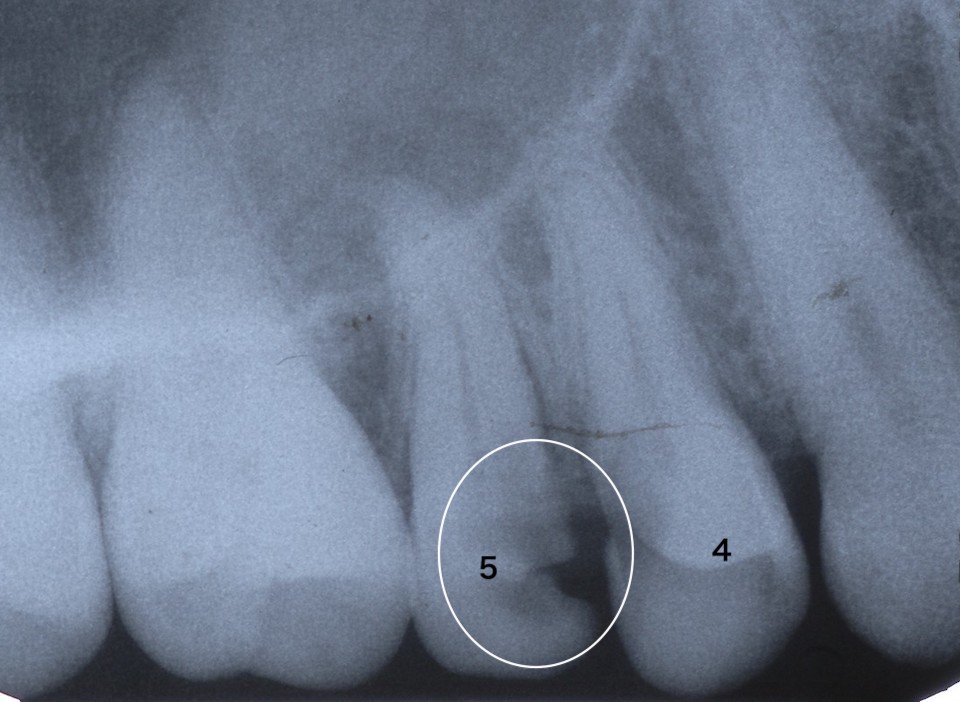

レントゲン写真だが

内部の象牙質はほぼ失われているので、全体が壊れるのは時間の問題だ。なぜならエナメル質は硬いが脆いので仮りに修復したとしても咬合性外傷がある限り、今度は根元から破折する可能性は高い。